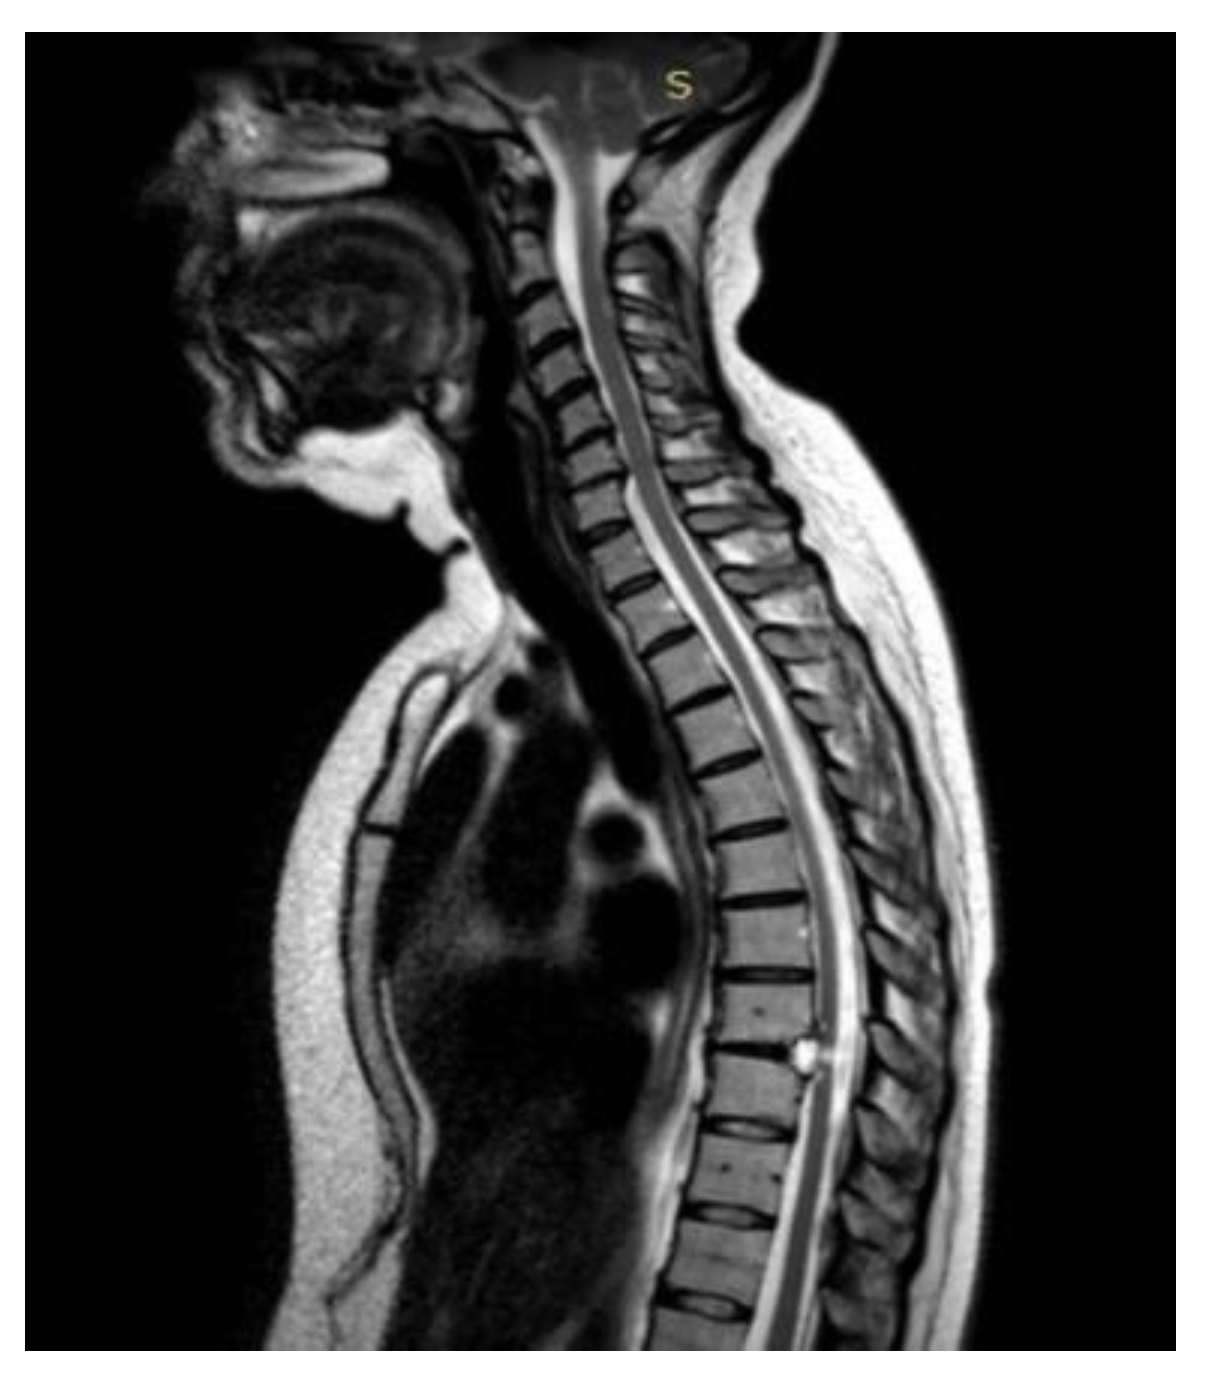

A 48-year-old man with a history of multiple neurosurgical interventions since his childhood presented with left upper limb weakness and gait worsening seven months after the removal of a cervical spinal catheter previously inserted (Torkildsen shunt). Over the next five months, his condition deteriorated, resulting in an inability to walk independently. Neurological examination revealed left upper limb weakness and spastic paraparesis in the lower limbs. The MRI of the cervico-dorsal spine showed myelopathy at C5-C6 level with a dorsal cystic lesion [Figure 2]. Surgery was performed to remove the cyst and perform the lysis of arachnoid adherence. A left-sided hemilaminectomy (C5-C7) exposed and excised the cyst compressing the spinal cord. Postoperatively, the patient initially improved but later developed tetraparesis. The MRI performed two months later showed persistent cord swelling and myelopathy extending to D1-D2 [Figure 3]. A second surgery included decompressive laminectomy (C6-C7) and removal of intradural adhesions. Despite these interventions, the patient’s tetraparesis remained stable with slight upper limb improvement. Follow-up MRI revealed ongoing signal changes from C3-C4 to D4-D5. A third surgery revealed intraoperatively new arachnoid adhesions and included an exploratory biopsy. Despite no further neurological decline, MRI continued to show persistent intramedullary signal abnormalities at three-year follow-up.

Figure 3. Case 2: pre- and post-operative MRI showing reduction of the myelopathy area.